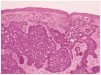

Se realizó extirpación de la tumoración y estudio histopatológico que demostró una lesión con características arquitecturales de benignidad, bien delimitada y simétrica localizada en la dermis (fig. 3). Estaba compuesta por células de aspecto basaloide, con ocasional formación de empalizada periférica. La inducción de la estroma originaba estructuras similares a las papilas foliculares. En la parte más superficial existía acumulación de pigmento melánico, tanto en los nódulos epiteliales como en melanófagos del estroma (fig. 4). El diagnóstico anatomopatológico fue de tricoblastoma pigmentado.

Fig. 4.--Epitelio con células basaloides y estroma con diferenciación folicular. En la parte más superficial se aprecian acumulaciones de pigmento melánico, tanto en los nódulos epiteliales como en los macrófagos del estroma.